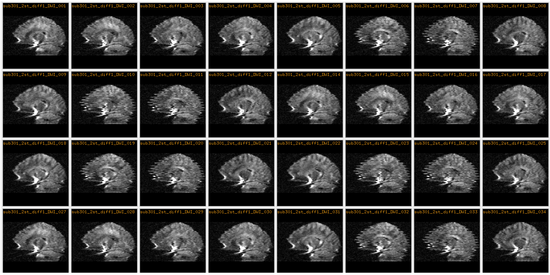

The DWI data consists of 13 volumes -- a b0 and 12 gradient directions. This process was conducted 3 times per patient for a total of 39 volumes. The image below shows a particular slice in all 12 gradient directions and all 3 scans where the artifacts can clearly be seen in some of the gradient directions.

Orig all.png